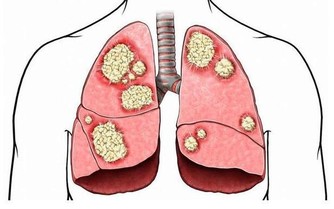

五、感染細菌

如果男性出現不潔性生活的話,很容易導致一些細菌侵入尿道部位。這些細菌會進入前列腺部位,導致前列腺部位因感染細菌而出現炎症。

另外,如果男性長時間不清洗自己的生殖部位,或者是不勤換內褲的話,一些病原體也會經過尿道進入前列腺部位,從而引起前列腺炎的出現。